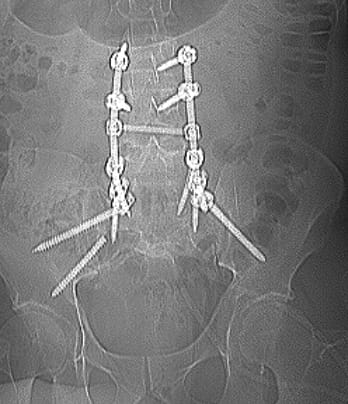

Це була складна операція. Вона тривала 7 годин. Розхитані та поломані гвинти було видалено, а також конструкцію було додатково укріплено ще гвинтами. Перепроведено тазовий гвинт. Також була виконана декомпресія корінця S1 що давав виражений больовий синдром.

Результати реоперації на наступних малюнках:

В результаті операції біль у спині повністю пройшла. Больовий синдром у стопі значно зменшився. Пацієнт ходить без ходунців, активно переміщується і почуває себе набагато краще.